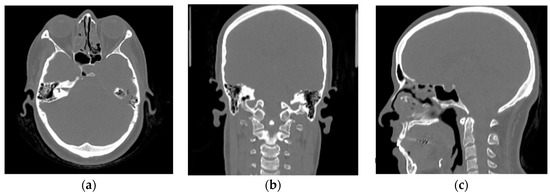

2.2.1. Training Dataset

2.2.2. Validation Dataset

3.1. Convolutional Neural Network (CNN) Results

3.2. Franken-CT Approach Results